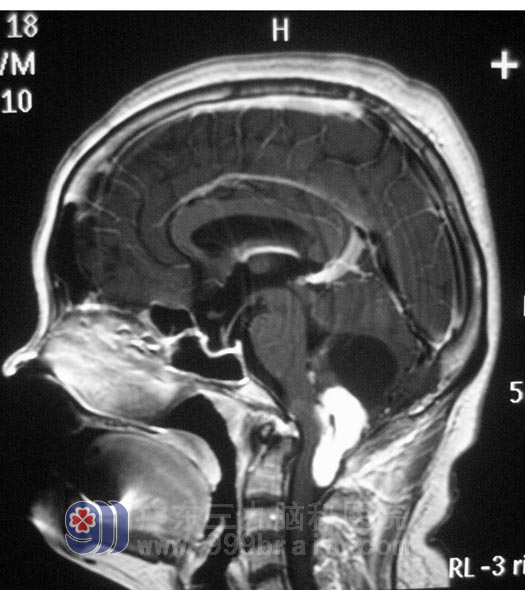

年过50的卢女士,5个月前开始出现左侧肢体麻木、乏力,偶有头痛、头晕,无恶心、呕吐,在当地医院治疗后,症状没有明显好转,并逐渐出现行走困难,视物重影,左侧眼球外展受限,构音障碍,饮水呛咳,吞咽有哽住感,左侧耸肩稍差,左侧胸锁乳突肌有萎缩。7月29日,医院头颅MR检查示“枕骨大孔区占位,大小约3cm×3cm,呈囊实性”,广东三九脑科医院综合神经外科鲁明主任结合影像和病史表现,初步考虑为“血管母细胞瘤”。

8月23日,鲁明主任主刀,在全麻下行“后正中入路延髓肿瘤切除术”,术中可见囊壁暗褐色病变组织,小脑组织有所塌陷,肿瘤实性部分位于延髓至第二颈椎髓外硬膜下,呈暗褐色,血供丰富,在显微镜下小心分离,完整切除,直径约3cm,术中后组颅神经、脑干及重要血管均予解剖保留完整,术中出血约400ml,手术历时9小时。术后2小时患者完全清醒,能遵嘱活动,四肢活动正常。术后第三天,患者神志清醒,自诉头痛、头晕症状好转,构音清晰,已恢复正常进食。术后经病理证实为:(枕骨大孔区)毛细血管性血管母细胞瘤。